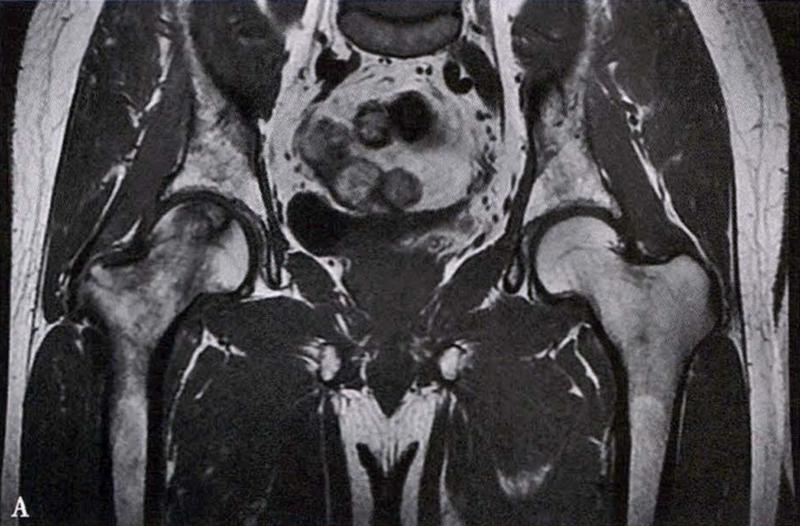

(2)MRI检查

MRI检查是早期诊断股骨头坏死最具特异性、灵敏度的检查方法。当怀疑有股骨头坏死,而X线片无明显异常时,应行MRI检查。诊断时可根据髋关节X线、MRI显示的坏死面积和塌陷程度进行ARCO分期。

冠状面及横断面MRI图像

MRI示双侧股骨头坏死,冠状面显示右侧股骨头坏死(图A、C),横断面显示双侧股骨头坏死(图B、D);T1加权像(图A、B)显示硬化带为低信号,T2加权像(图C、D)显示右侧骨坏死硬化带外围高信号的骨髓水肿,左侧无骨髓水肿。